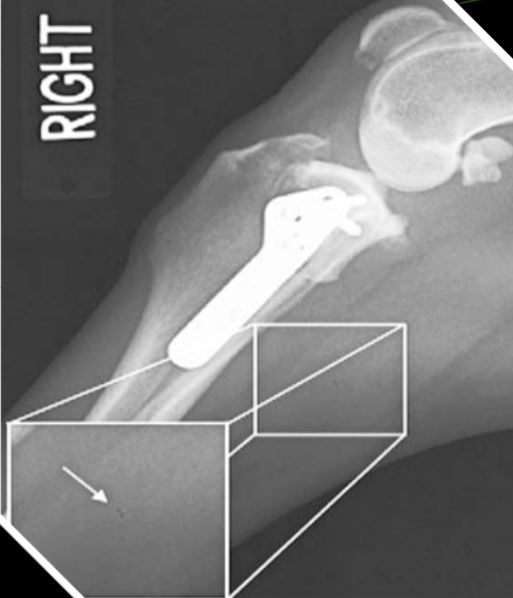

12

Q

Artifact and fix?

A

Roller artifact.

Call someone and get new film